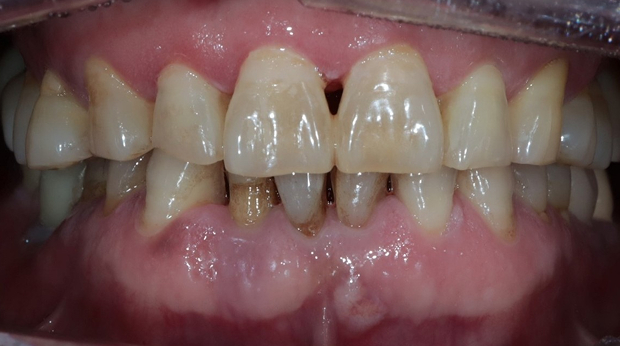

임플란트와 사랑니 발치는 외과적 시술로 잇몸을 절개하는 외과적 시술은

짧으면 짧을 수록 시술 후 붓기와 통증이 최소화됩니다.

치과의사 경력 14년차 구강외과 전문의가 빠르고 안전하게, 아프지 않게 수술해 드립니다.